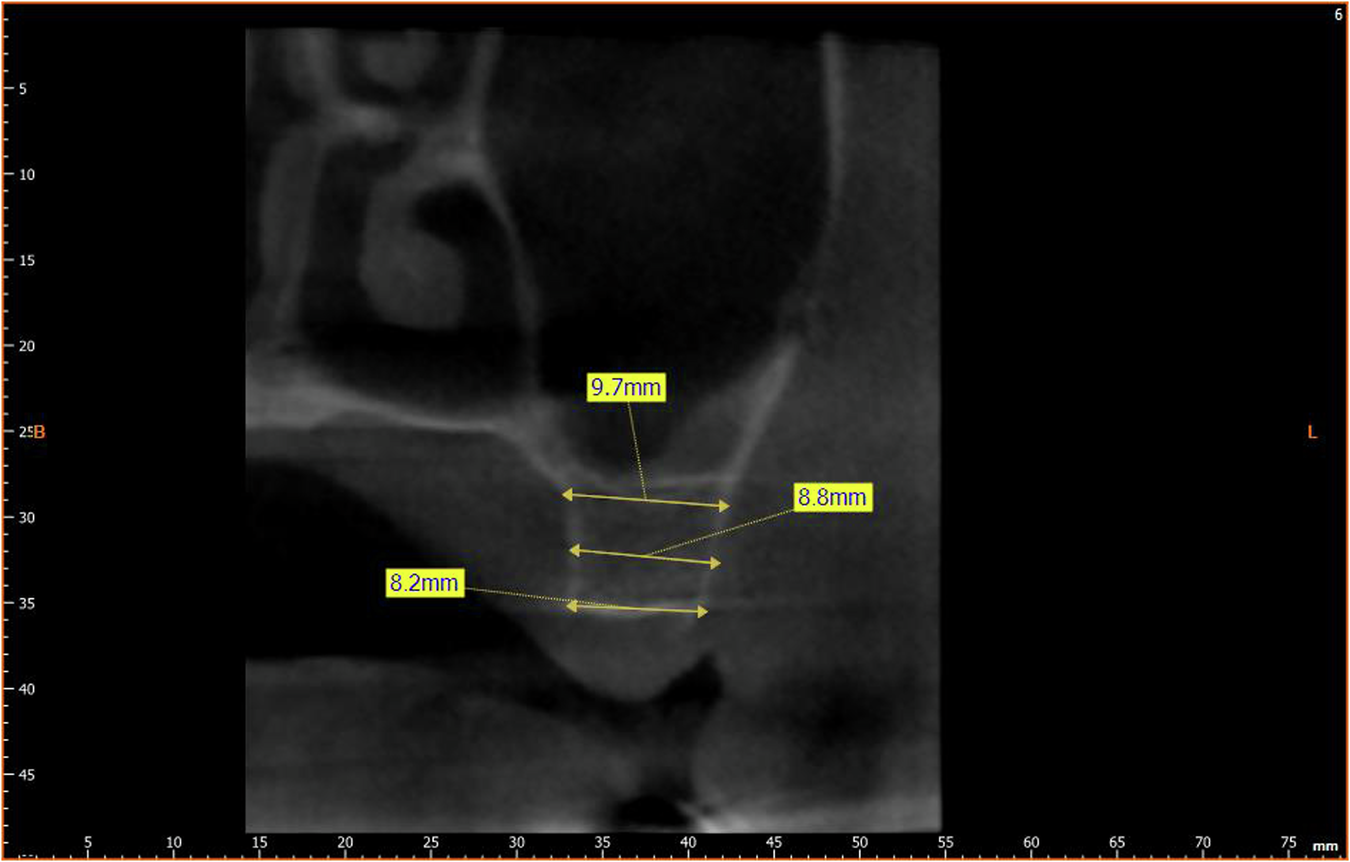

Fig. 3: BD Measurement.

Measurement of bone diameter (BD).